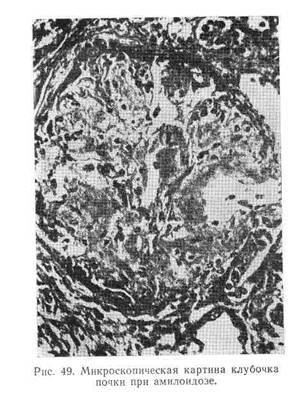

Гистохимические и электронно-микроскопические исследования ткани почек, полученной при помощи пункционной биопсии, показали, что в относительно ранней стадии амилоидной дистрофии поражаются не все петли клубочка. Стенки пораженных петель неравномерно утолщены. В более поздней стадии амилоидная субстанция наводняет весь клубочек, закрывая просвет капилляров, откладывается в стенке артериол, вокруг них, а также в базальной мембране канальцев и в интерстициальной ткани. Нефроны запустевают и атрофируются, в мозговом и корковом веществе разрастается интерстициальная ткань (рис. 49),